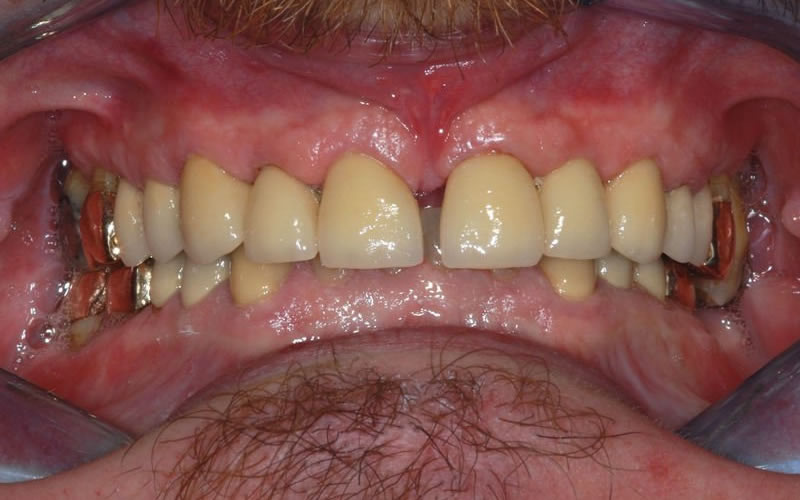

Case Studies

Upper crowns and lower composites (4 images)